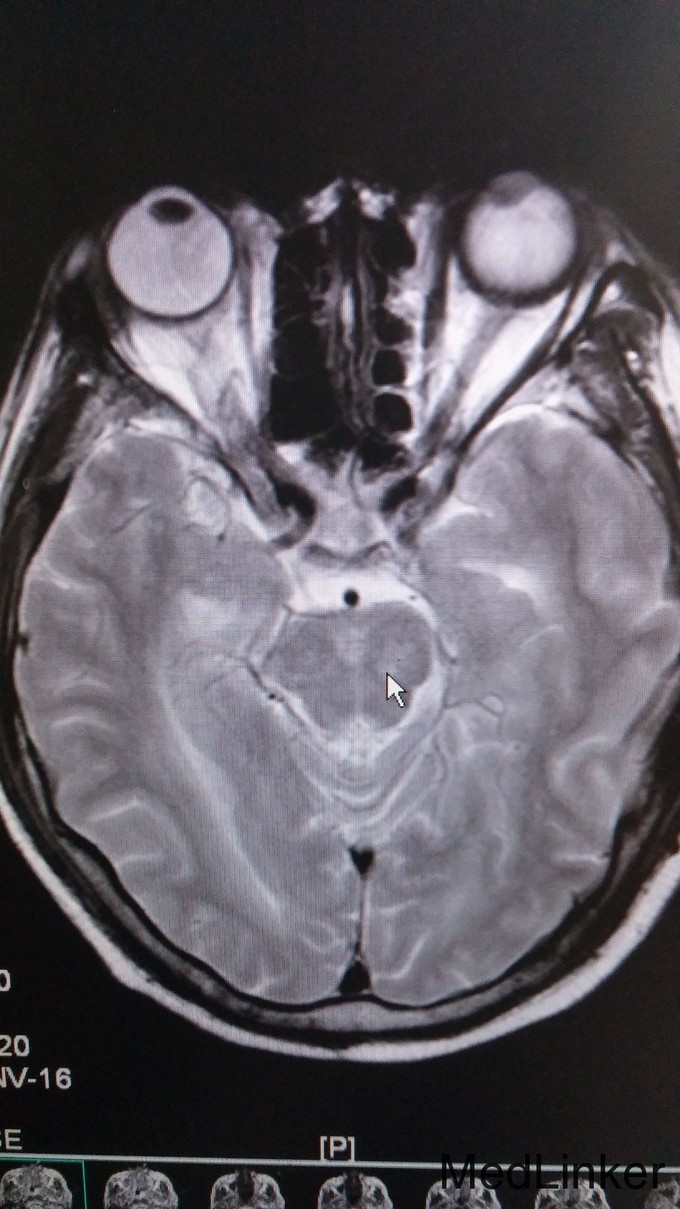

神志昏睡、语无伦次,定向力、判断力正常、计算力、记忆力无法检查。左侧肌张力增高。四肢肌力2级。指鼻、跟膝胫试验检查不配合。双侧腹壁反射存在。双侧肱二头肌、肱三头肌、膝腱、跟腱反射减弱。颈抵抗,颏胸距3横指,Kernig和Brudzinski征阴性。辅查: 1. 血常规:HSCR 3.24mg/L,白细胞计数9.1G/L,中性粒细胞计数8.32G/L,中性粒百分数91.4%;CK 504IU/L, CK-MB 27.9 IU/L, LDH 293 IU/L; 2. 腰穿:脑压225mmH20,氯119.9mmol/L,葡萄糖5.5mmol/L, 乳酸4.7 mmol/L, 蛋白1460 mg/L, 白细胞 60M/L 3. 颅脑MRI:双侧大脑半球(基底节区及放射冠区分布较多)、小脑、桥脑、中脑、延髓多发异常信号灶,增强扫描颅内血管明显增多、迂曲,脑膜增厚强化,可符合播散性脑脊髓炎改变,不排除其内白质疏松及腔隙性脑梗塞因素。肌电图:神经性受损(运动神经为主);脑电图:轻-中度异常脑电图;胸片示:下肺野纹理增粗、模糊,不排除炎症。